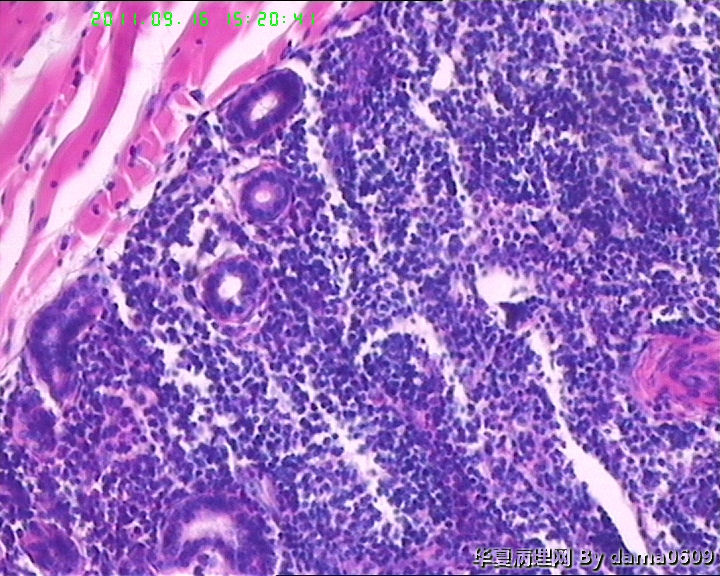

• 背部肿物,急请老师看看!!图4

图4

考虑T细胞淋巴瘤:依据1.淋巴样细胞浸润破坏性生长达肌组织;2.淋巴样细胞异型:核形不规则,大小不一,胞浆较丰富.注:表面上皮有增生需排除炎性反应.

结合病史及镜下表现,如淋巴细胞浸润以皮下浅层为重、向下渐轻等,是否可符合书上的一个诊断:皮肤假性淋巴瘤(皮肤B细胞假性淋巴瘤)?学生自己没见过,还请老师多指教!!!谢!!

假上皮瘤样增生,其下大量淋巴样细胞浸润,结合有外用药病史,考虑急性淋巴细胞反应性增生。